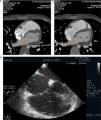

Case 2A 50-year-old man with a history of type 2 diabetes, permanent atrial fibrillation and chest pain, was referred for cardiac CT to exclude coronary disease. The exam revealed non-significant coronary disease, dilated LA and a subtraction image in the left atrial appendage suggestive of thrombus (Figure 2). The diagnosis could have been confirmed by a second scan a few minutes after the first or by transesophageal echocardiography, but these were not performed because the results would not have altered the therapeutic approach. The patient was prescribed oral anticoagulation.